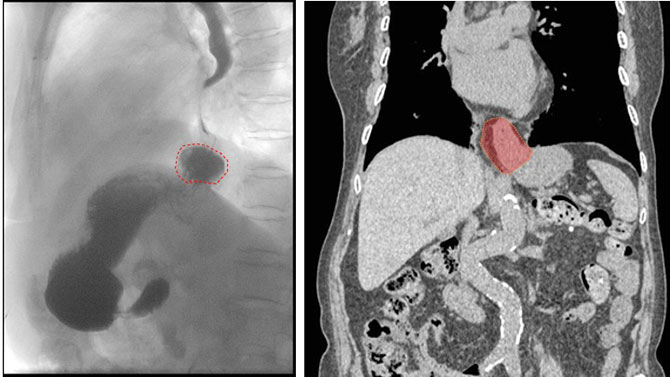

左:上消化道造影:红圈为疝入胸腔的胃底;右:胸腹CT平扫:阴影部分为疝入胸腔的胃底及网膜组织。

入院综合外科后,经详细检查,老人被确诊为食管裂孔疝——即本应位于腹腔的胃通过膈肌的食管裂孔“钻”进了胸腔,导致胃食管反流和消化道梗阻。若不及时手术,不仅无法进食,还可能引发嵌顿、坏死等致命风险。然而,94岁高龄、心肺功能储备差,让这场手术如同一场“走钢丝”。